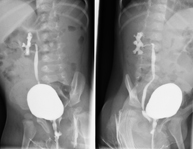

- UIV (Pielografia descendent)

La urografia intravenosa (UIV) consisteix en l'obtenció d'imatges radiològiques seriades del ronyó, vies urinàries i bufeta. Aquest estudi requereix sempre l'ús d'un contrast iodat. - Cistografía (CUMS)

La cistouerotrografia miccional seriada consisteix en l'obtenció d'imatges radiològiques per valorar l'anatomia i la funció de la uretra i la bufeta amb l'administració de contrast iodat a través d'una sonda vesical. - Uretrocistografia (Uretro-Cums)

La uretrocistrografia retrògrada i miccional consisteix en l'obtenció d'imatges radiològiques per valorar l'anatomia i la funció de la bufeta i de la uretra. S'aplica material de contrast a través d'una petita sonda que es troba a la uretra i s'obtenen imatges durant l'ompliment i el buidatge de la bufeta. - Pielografia ascendent per catèter